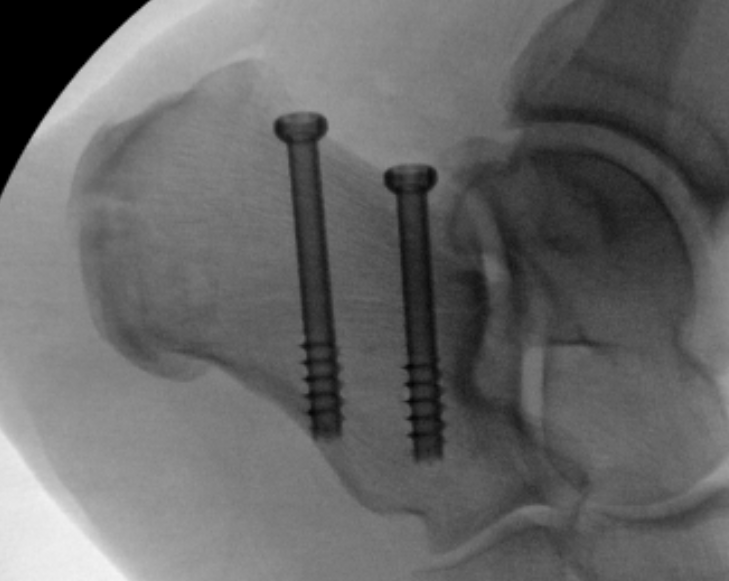

ORIF

Reduce fracture with clamps

Insert 2 - 3 screws

- bicortical fixation

- anterior to weight bearing posterior tuberosity

- cast with foot plantar flexed